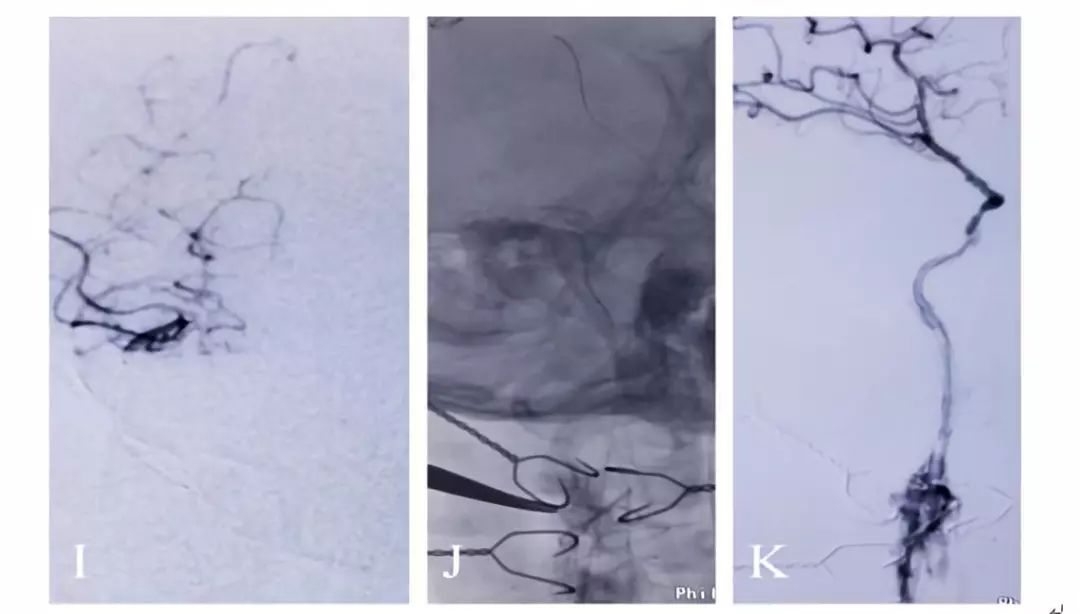

术前造影显示颈动脉C1-C4闭塞

颈动脉内膜剥脱后可见闭塞处血流缓慢。

近端闭塞处置入支架后,可见海绵窦段极重度狭窄

术中用小球囊2.5-20mm的球囊扩张海绵窦段狭窄处。

球囊扩张后,海绵窦段血流通畅。

术后一月复查CTA,见颈动脉闭塞段通畅。